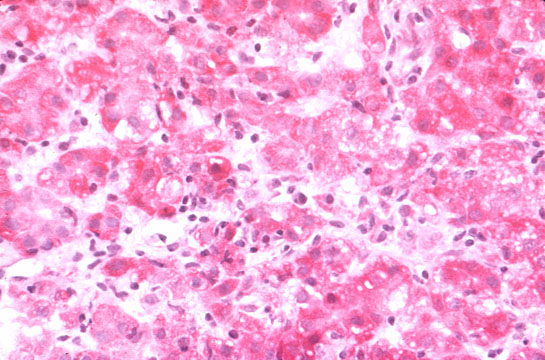

Focal necrosis

Fig 44 - FOCAL NECROSIS: A focal area where a group of hepatocytes are necrotic and the area is infiltrated by inflammatory cells which in this case are mainly lymphocytes. Other times the reaction may be histiocytic as for example in granulomatous lesions. A light lesion.